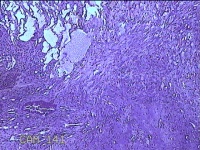

右输卵管异位病灶?

性别

女

年龄

26岁

临床诊断

右侧子宫内膜异位病灶

一般病史

停经52天。

标本名称

大体所见

灰白暗红色不规则碎组织2.3x2x0.3cm一堆。